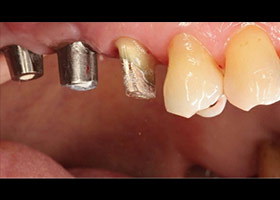

植牙合併無敲擊水壓式上頷竇增高術